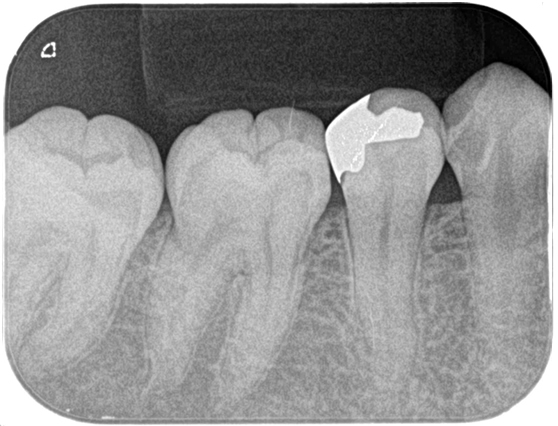

根管治療 症例9

| 治療後 | ![]() |

根管治療することにより治療の影響で一時的に痛みが強くなることがあります。